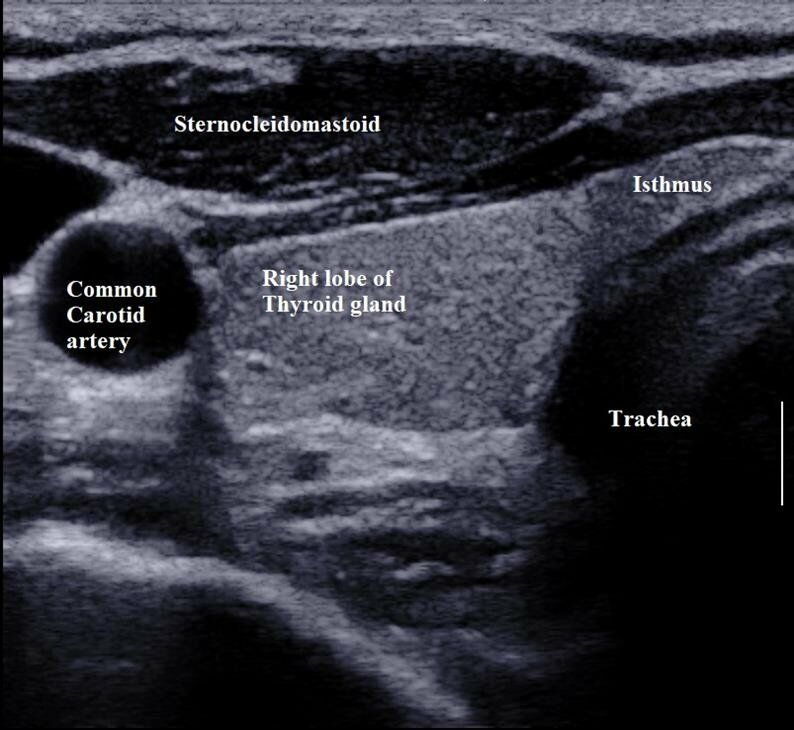

41.一位 65 歲男性發現右頸部有一硬塊,頸部超音波檢查如附圖,細針穿刺細胞學檢查顯示為甲狀腺乳突癌 (papillary thyroid cancer),根據超音波圖像,此甲狀腺癌可能合併下列何者特性?

(A)lateral neck lymph node metastasis

(B)extrathyroidal extension

(C)tracheal invasion

(D)esophageal invasion

正常甲狀腺 soon

(from Researchgate.net:https://www.researchgate.net/figure/5-Grey-scale-ultrasound-features-of-normal-thyroid-gland-and-its_fig8_324274379)

正常狀況需有點高回音

題目中 thyroid 已經表現 Cancer lesion (hypo)